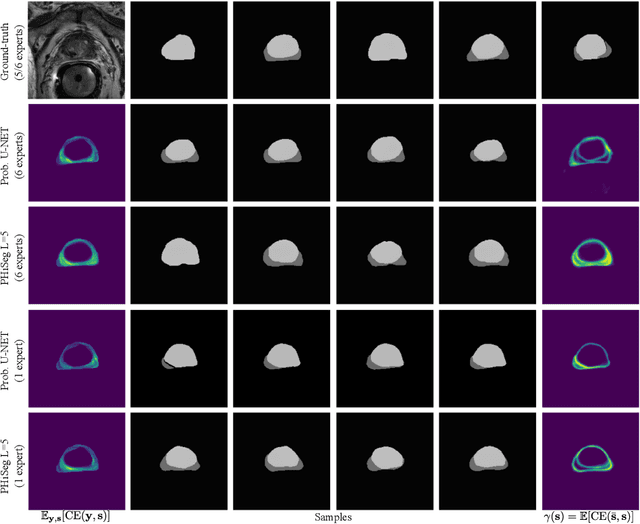

Abstract:Segmentation of anatomical structures and pathologies is inherently ambiguous. For instance, structure borders may not be clearly visible or different experts may have different styles of annotating. The majority of current state-of-the-art methods do not account for such ambiguities but rather learn a single mapping from image to segmentation. In this work, we propose a novel method to model the conditional probability distribution of the segmentations given an input image. We derive a hierarchical probabilistic model, in which separate latent spaces are responsible for modelling the segmentation at different resolutions. Inference in this model can be efficiently performed using the variational autoencoder framework. We show that our proposed method can be used to generate significantly more realistic and diverse segmentation samples compared to recent related work, both, when trained with annotations from a single or multiple annotators.